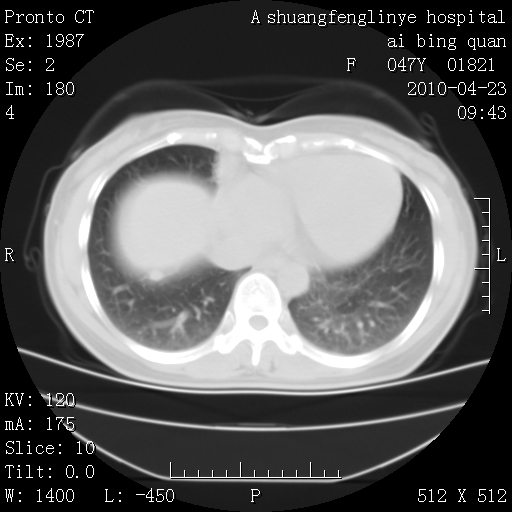

标题: CT25944:胸痛、气短、前几日高烧!肺Ca?请会诊! [打印本页]

标题: CT25944:胸痛、气短、前几日高烧!肺Ca?请会诊!

双肺多发结节,考虑转移瘤,肺癌肺转移不除外

周围型肺癌并肺转移

双肺多发结节,部分密度较高,最大结节边缘光滑。临床有“胸痛、气短、前几日高烧”病史。首选考虑:右肺感染性病变!建议积极消炎后复查!